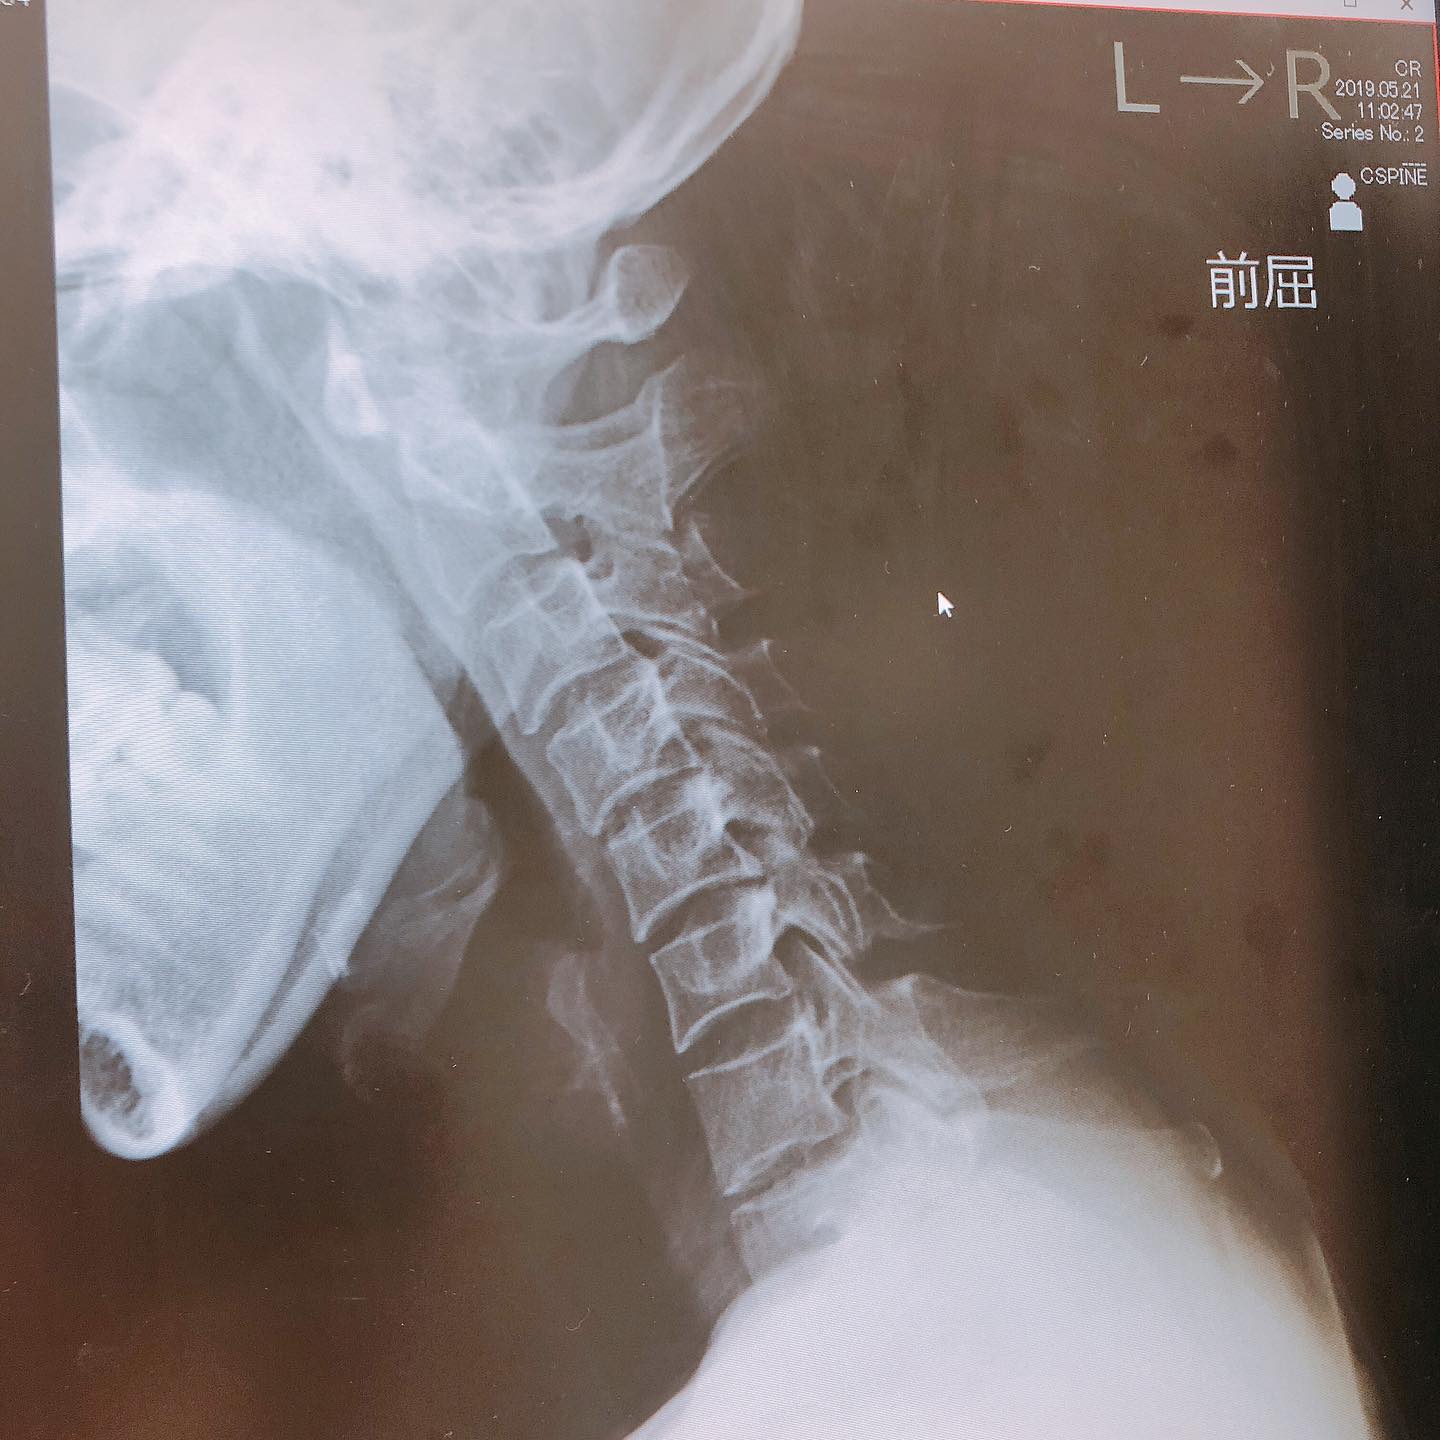

首が曲がらない

左へ首を回そうとすると

痛みが出て曲がらなくなっていました。

焦って病院でレントゲン。

まだ大丈夫ですよと、

安心したものの

進行したらどうしようと不安で。